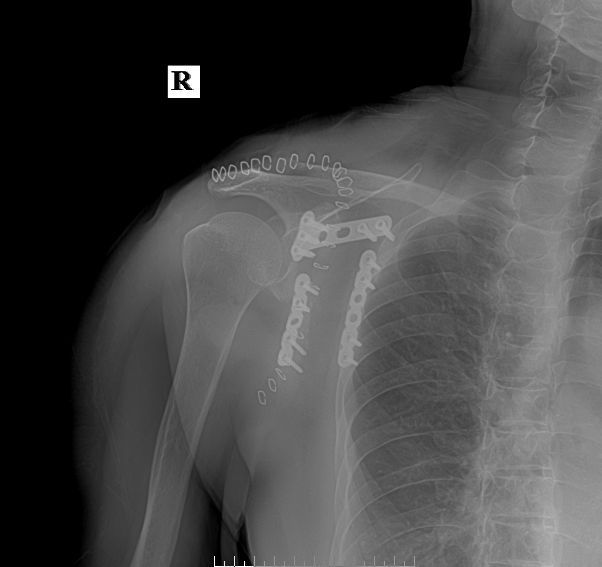

术后复查X线片示骨折复位良好,内固定在位且牢靠。根据骨伤科三期辨证理论,早期因瘀血停滞影响骨痂生长,故以活血化瘀,消肿止痛为主,应用桃红四物汤。术后证属肝肾亏虚,气血不足,治以补益肝肾,补气养血,应用愈骨胶囊等药物促进骨折愈合。休息3个月,加强营养,促进骨折愈合;继续中药应用,促进骨折愈合;定期复查,(1月、3月、6月);不适随诊。 本病例中医药应用结合手术复位,早期将骨折复位,中医药早期应用活血化瘀、消肿止痛,可迅速缓解患者症状。中医药中后期应用可促进骨折愈合,加快术后恢复,可使患者获得满意的术后疗效。